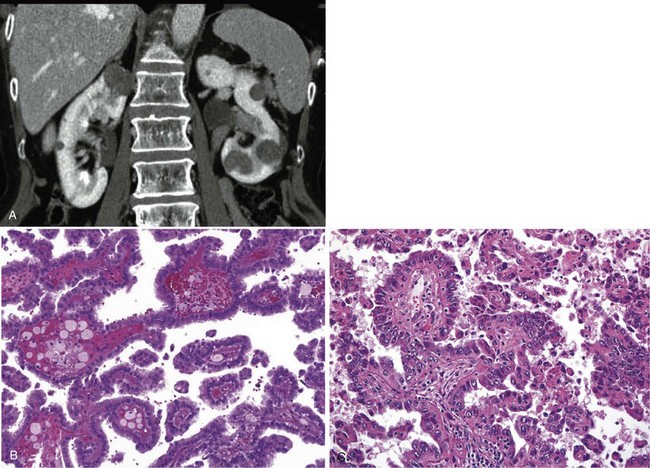

A dedicated (thin-slice) renal CT scan remains the single most important radiographic test for delineating the nature of a renal mass. CT, with and without the administration of contrast material, is necessary to take full advantage of the contrast enhancement characteristics of highly vascular renal parenchymal tumors (Davidson et al, 1997; Zagoria, 2000, Prasad et al, 2008; Ng et al, 2008; Zhang et al, 2007a). In general, any renal mass that enhances with intravenous administration of contrast material on CT by more than 15 Hounsfield units (HU) should be considered an RCC until proved otherwise (Fig. 49–2) (Hartman et al, 2004). Solid masses that also have substantial areas of negative CT attenuation numbers (below −20 HU) indicative of fat are diagnostic of AMLs (Nelson and Sanda, 2002). In 10% to 20% of solid renal masses CT findings are indeterminate, and additional testing or surgical exploration is needed to establish a definitive diagnosis. On occasion, CT demonstrates an enhancing renal segment that is isodense with the remainder of the kidney, suggestive of a renal pseudotumor. Renal pseudotumors may be due to a hypertrophied column of Bertin, renal dysmorphism, or an unusually shaped kidney (Bhatt et al, 2007). In this situation, the diagnosis of a pseudotumor can be confirmed by isotope renography with technetium-labeled dimercaptosuccinic acid or glucoheptonate (Fig. 49–3). These isotope studies demonstrate an area of increased density if the mass is a pseudotumor and an area of decreased density if the mass is a cyst or solid tumor (Israel and Bosniak, 2003a).

Figure 49–2 A, Unenhanced CT scan shows solid, right posterior renal mass. B, After administration of the contrast agent, CT scan shows that the mass enhances more than 20 HU and is thus highly suggestive of RCC. This mass was excised and confirmed to be a clear cell renal cell carcinoma.

(Courtesy of Dr. Terrence Demos, Maywood, IL.)